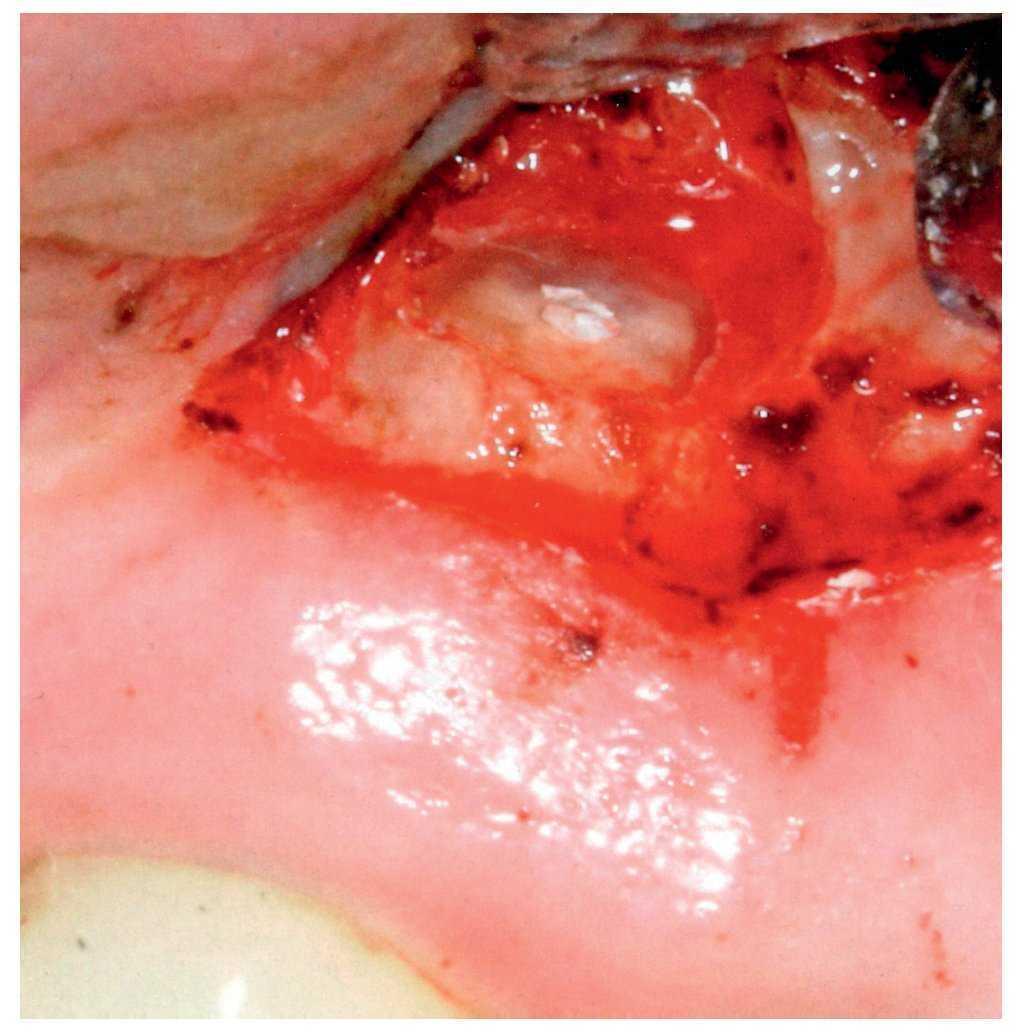

La Colaboración Cochrane publicó una revisión sistemática en 2007 en la que se incluyó bibliografía revisada hasta abril de 20077. Se identificaron tres artículos relativos a estudios clínicos aleatorizados que cumplían los criterios de inclusión definidos previamente por el grupo de autores5,21,22. Dos de estas tres publicaciones informaron de aspectos distintos del mismo estudio21,22. Para la evaluación se resumieron los resultados de los dos estudios. De acuerdo con ésta, se trataron 126 casos de lesiones radiolúcidas periapicales mediante una reendodoncia ortógrada o una apicectomía después de un tratamiento endodóntico previo y se siguieron prospectivamente durante un período de un año. En 82 de estos casos el seguimiento se prolongó durante 4 años. Al cabo de 1 año, la tasa de éxito de la intervención quirúrgica fue ligeramente superior a la del retratamiento no quirúrgico. Al ampliar el período de seguimiento a 4 años, la tasa de éxito de las dos variantes terapéuticas fue similar (fig. 4). Sin embargo, durante la primera semana postoperatoria después de la intervención quirúrgica se registró una incidencia significativamente mayor de tumefacción y dolor que después de la reendodoncia ortógrada. Del mismo modo, se tomaron significativamente más analgésicos y antiinflamatorios después de la intervención quirúrgica7.

Figura 4. La intervención quirúrgica de una lesión radio-lúcida apical se acompaña de un número significativamente mayor de molestias y de una mayor necesidad de analgésicos que la reendodoncia ortógrada, pero sus resultados son idénticos al cabo de 4 años (imagen por gentileza del grupo Dres. Peleska/Tschechne/Bärwald, Marburgo).